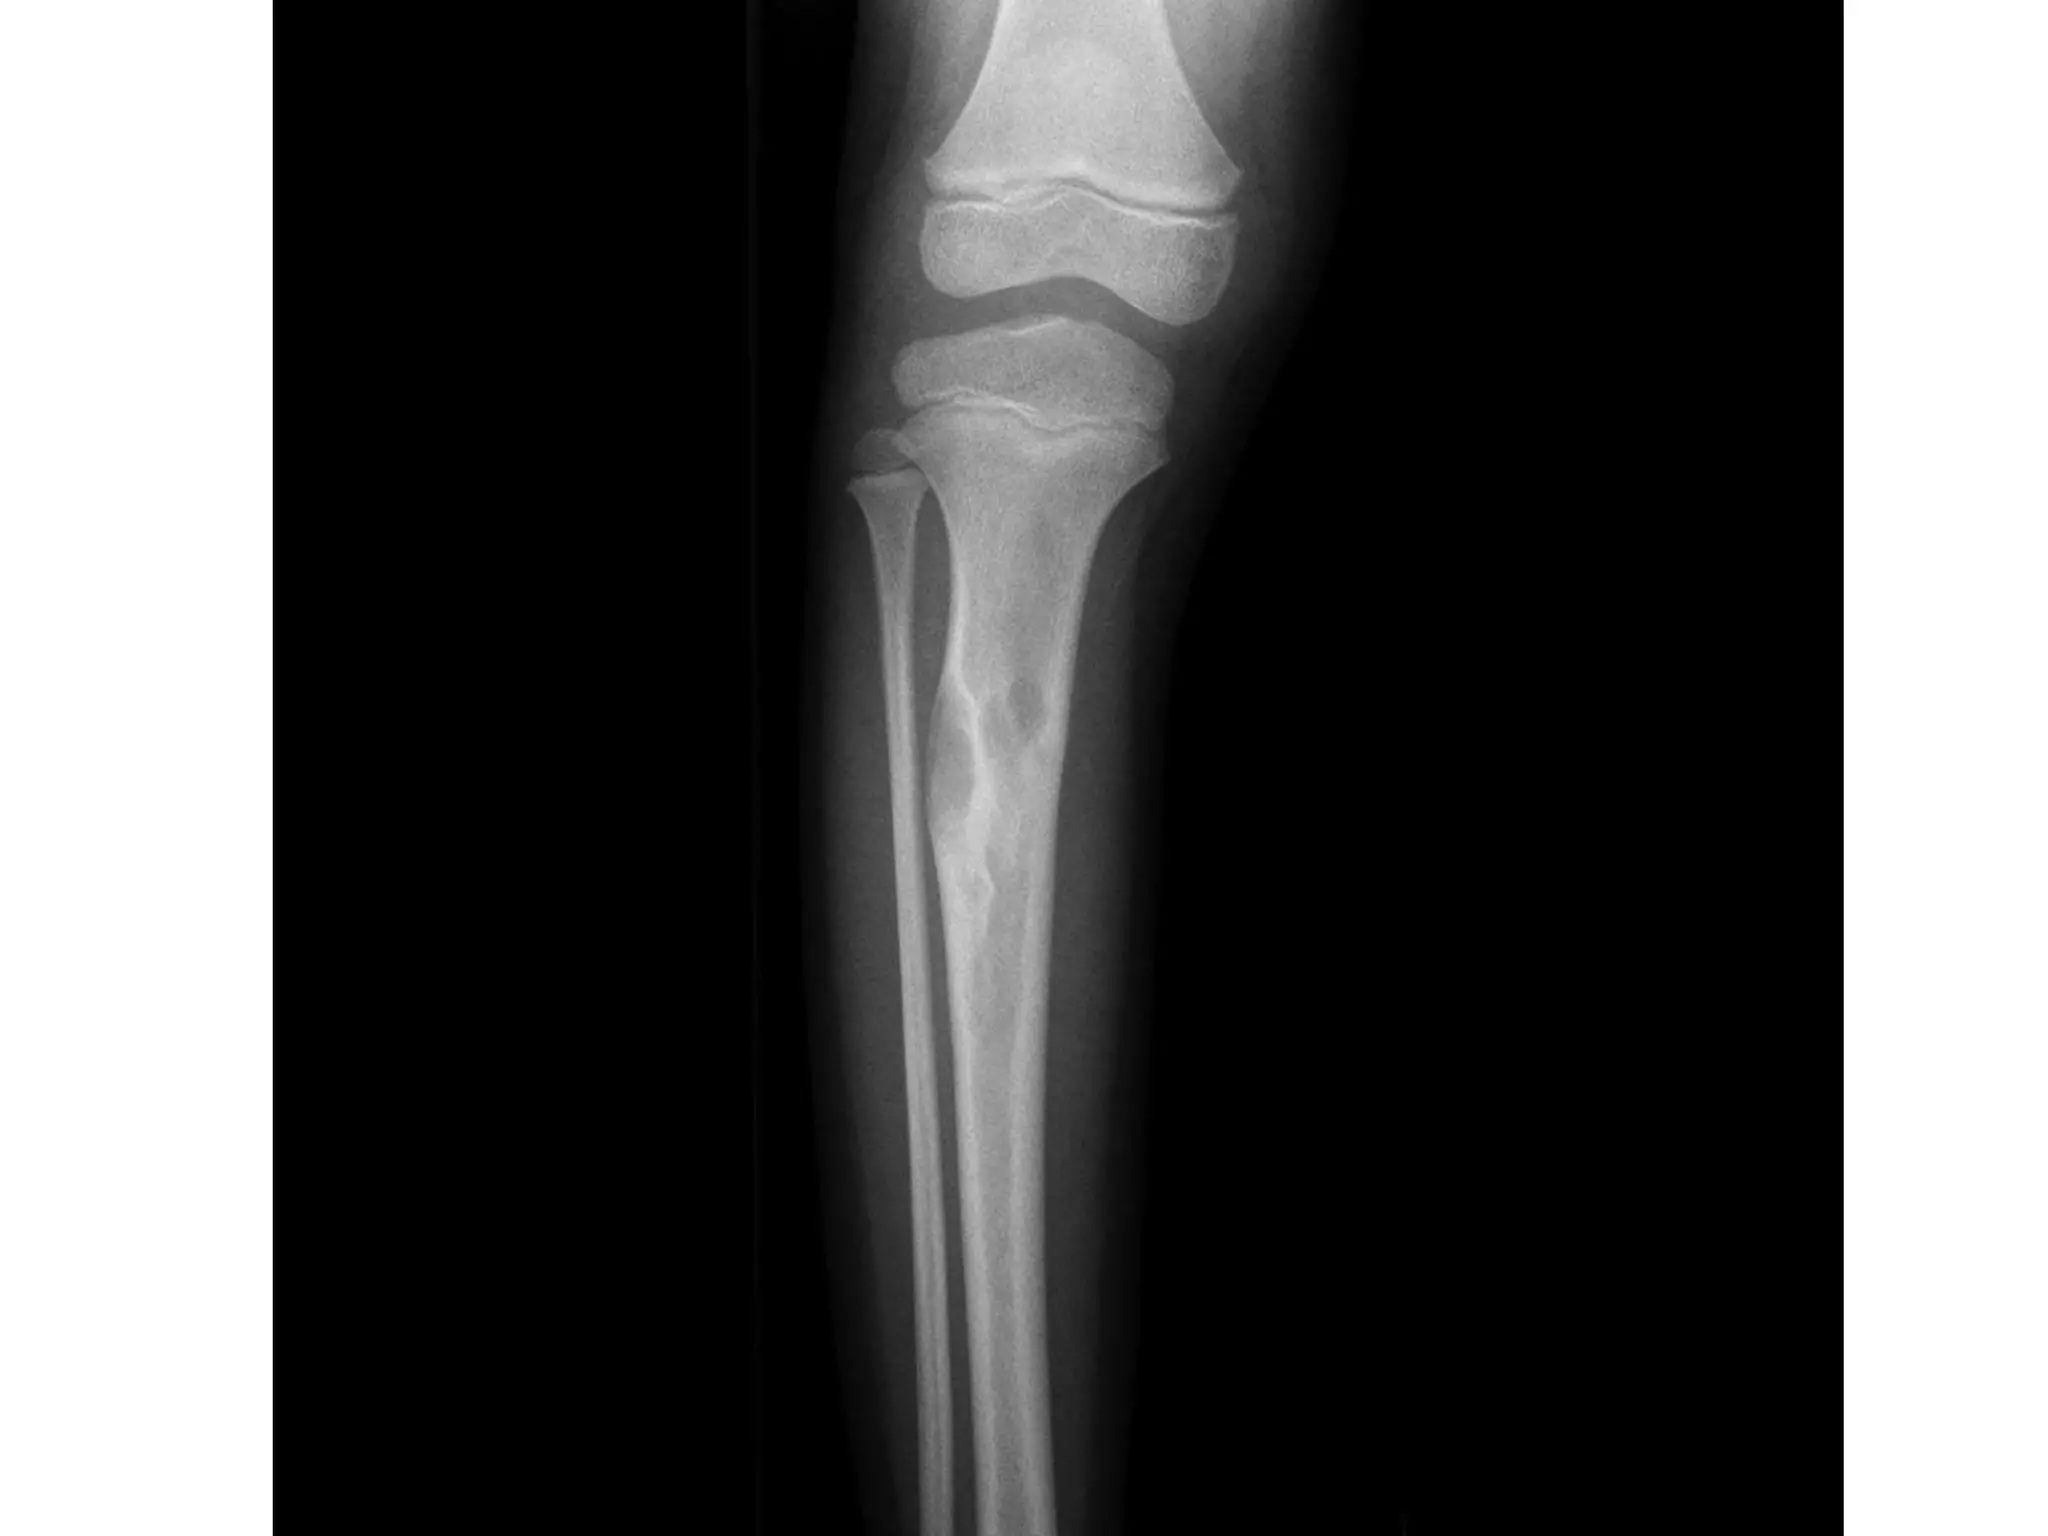

• X-rays demonstrate a well outlined, lytic

centrally placed, metadiaphyseal lesion

expanding and thinning the cortices

• It often abuts but does not cross the physis.

• Bone septa are often present which give the

impression of a multiloculated cyst.

• When fracture occurs, a small fragment may be

seen within the cavity, the classic ‘fallen leaf’ sign.

• MRI will demonstrate the homogeneous fluid-filled

cavity.

SIMPLE BONE CYST •This is a solitary, usually unilocular cystic bone cavity lined by a fibrous membrane and filled with serous or serosanguinous fluid. • Males are more frequently affected and the majority occur within the first two decades of life. • Although they can arise at any location, the vast majority of simple bone cysts (SBCs) occur in the proximal humerus, the proximal femur or the proximal tibia, most commonly affecting the metaphyseal areas close to the physis. • In the majority of cases the lesion is asymptomatic, being discovered incidentally. • However, fracture through the lesion is not uncommon and often this is the presenting feature. Occasionally, mild pain or swelling may be present.

• 25.

• X-rays demonstratea well outlined, lytic centrally placed, metadiaphyseal lesion expanding and thinning the cortices • It often abuts but does not cross the physis. • Bone septa are often present which give the impression of a multiloculated cyst. • When fracture occurs, a small fragment may be seen within the cavity, the classic ‘fallen leaf’ sign. • MRI will demonstrate the homogeneous fluid-filled cavity. • Histologically, the cyst lining demonstrates connective tissue with foci of reactive bone. • Following fracture, there will be features of fracture callus and new bone formation.

• 26.

• Treatment isoften supportive as lesions will regress following skeletal maturity. • Percutaneous injection of steroid has been reported with varying success but is best reserved for ‘active’ lesions, i.e. those abutting the physis in young children. • Curettage and bone grafting may be required in areas at risk of fracture, and pathological fractures of the proximal femur in particular will often require fixation and stabilization. • Recurrence is reported in 10–20% of cases. • Large cysts may result in limb shortening, and avascular necrosis of the femoral head can occur following fracture through proximal femoral lesions. • Spontaneous resolution following fracture has been reported